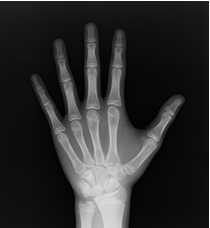

骨年齢を割り出す方法はいくつかありますが、基本的に左手のレントゲン写真(図)を使い、手を構成するいくつかの骨の形状から骨年齢を割り出します。

• 暦年齢12.3歳 骨年齢:10歳

図)アカデミー試験での骨年齢評価のための左手レントゲン写真。すべて小学6年生で、暦年齢はほぼ同じですが、レントゲン写真でも明らかなように手を構成する骨の成熟に違いがあるのがわかります。骨年齢は10~13.3歳と幅がみられています。